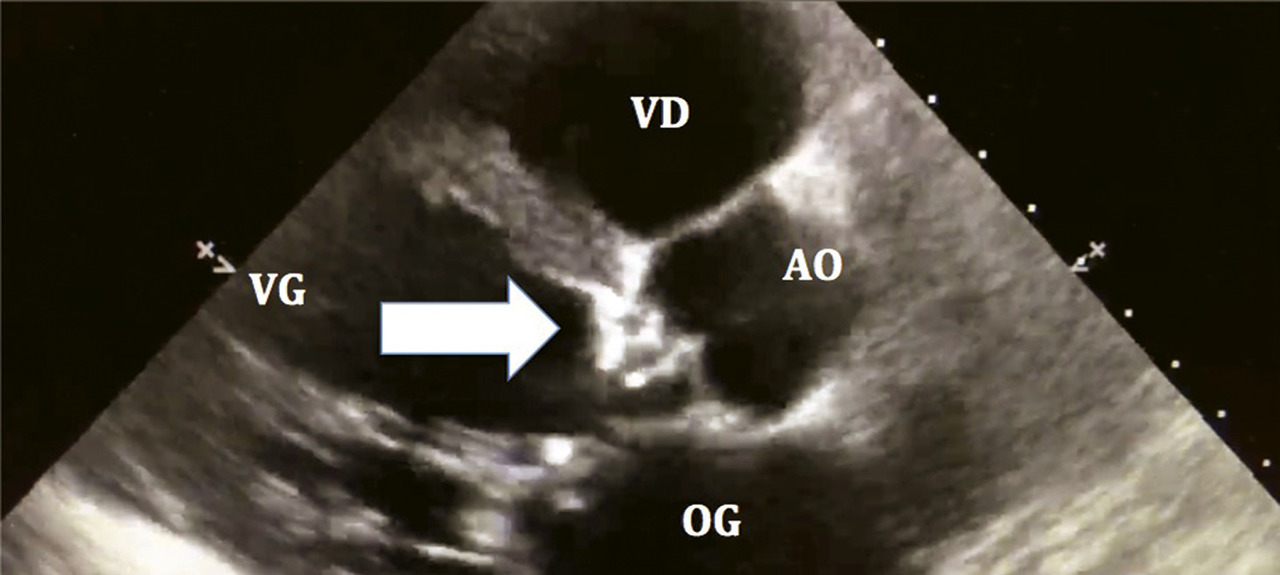

Diagnostic positif : on observe une valve aortique calcifiée dont l’ouverture est limitée, avec une accélération des flux en Doppler couleur (aliasing). Les vitesses sanguines à travers la valve sont augmentées (Vmax > 2,5 m/s) en Doppler continu (fig. 1).

Diagnostic de sévérité, quantification : un rétrécissement aortique est considéré comme serré, en présence d’un des critères suivants :

• Vmax ≥ 4 m/s (extrême si > 5,5 m/s) ;

• ou gradient moyen transvalvulaire ≥ 40 mmHg ;

• ou surface valvulaire aortique ≤ 0,6 cm2/m2 (ou < 1 cm2, mais la valeur indexée à la surface corporelle est préférée). Sachant qu’une surface valvulaire aortique normale est de l’ordre de 2 à 3 cm2.